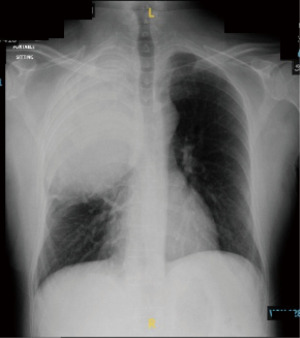

Patient was worked up pre-operatively with general labs, which included complete blood count (CBC), coagulation and thyroid function. A preoperative echocardiogram was also performed and was within normal limits. The radiograph revealed a large right upper heterogeneous opacity with mild tracheal indentation, but no mediastinal shift. The lungs appeared normal, and no obvious calcification was identified (Figure 1).